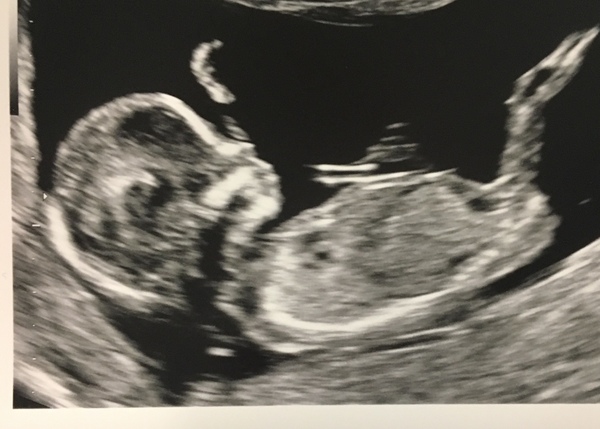

Just had our scan. All looking good and head count just the one 😄 baby is waving hello.

Dates have moved slightly (I’m now apparently 13+5 although my app says 13+4) so now due 25.04 but still expecting to go over though.

Hope it’s all going well for the others having scans today 🤞🏼

Hello baby Mimi!! Grin Absolutely love scan pics. Thanks for sharing.

It was amazing! Everything looks good and it jumped around all over the place!